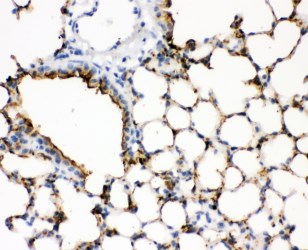

SP-A is a key component of pulmonary surfactant. In lung adenocarcinoma, particularly the bronchioloalveolar carcinoma subtype of lung adenocarcinoma, tumor cells often express SP-A. Immunohistochemical detection of SP-A aids in the diagnosis and differential diagnosis of lung adenocarcinoma, helping to distinguish it from other types of lung cancer such as squamous cell carcinoma and small cell carcinoma, as these cancers typically do not express SP-A. In some interstitial lung diseases, such as idiopathic pulmonary fibrosis and pulmonary alveolar proteinosis, the expression and distribution of SP-A are altered. For example, patients with pulmonary alveolar proteinosis have large amounts of SP-A-rich protein-like material deposited in the alveolar spaces. Immunohistochemical detection of SP-A can help clarify the nature of the lesion and differentiate it from interstitial lung diseases caused by other factors.

Surfactant Protein A antibody reagents can specifically bind to the Surfactant Protein A molecular antigen. Immunohistochemistry kits containing Surfactant Protein A antibody reagents are suitable for the auxiliary diagnosis of interstitial lung diseases (such as idiopathic pulmonary fibrosis/IPF) and pulmonary alveolar proteinosis (PAP).